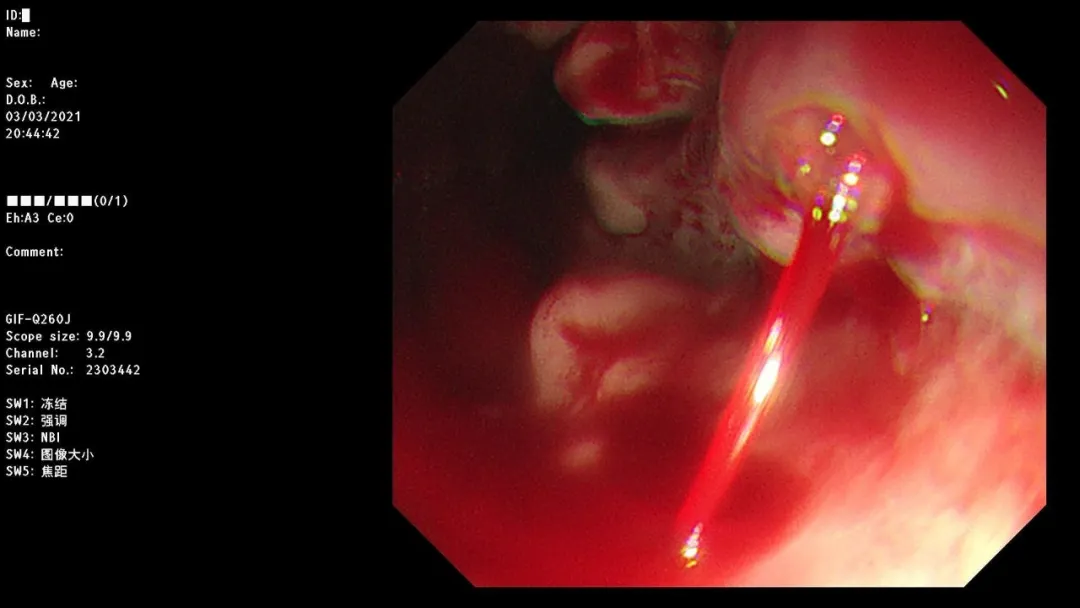

病例一:女,36岁,呕血2天,既往有乙肝病史,于南大一附院消化科就诊。

South Africa red wine

急诊胃镜示:食管距门齿32cm处可见一破口活动性出血,予套扎器套扎治疗,术后无活动性出血,检查诊断:食管静脉曲张破裂出血。